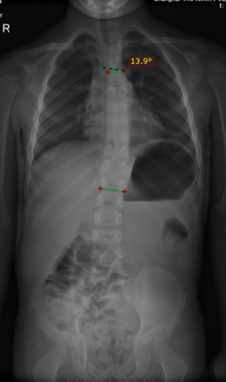

患者男,7岁,家族遗传性骨骼发育不良,体态姿势不正遂至本院就诊。2020年8月拍摄脊柱全长X线片,显示双下肢不等长、双髋关节、脊柱畸形,骨盆倾斜并引起脊柱侧弯,影像检查显示Cobb角胸弯13.9°。

矫形鞋垫

根据患者的年龄与发育情况分析定制3D打印个性化矫形鞋垫,通过三维扫描与计算机辅助设计与3D打印技术结合。根据下肢力线和骨盆影响给予矫形鞋垫右脚补高,恢复骨盆平衡,预防脊柱侧弯进一步发展并进行随访观察。